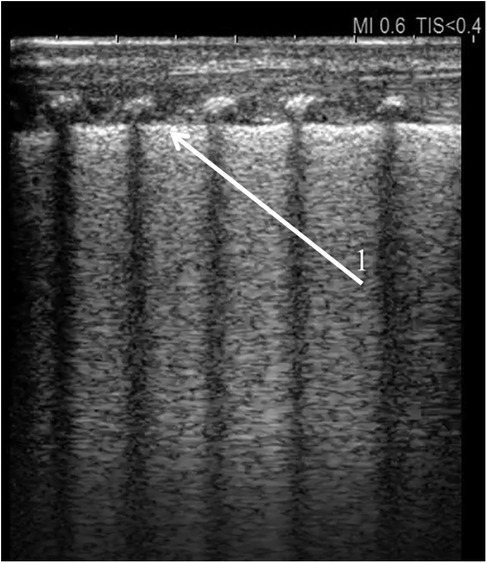

Surfactant deficiency syndrome in premature infants is a good example of the use of ultrasound as a diagnostic tool. In 2008, the Italian authors of one of the first publications demonstrated high sensitivity and specificity the LUS in identifying RDS. The atelectatic nature of the lung tissue, with varying degrees of interstitial thickening, is reflected on ultrasound in an increasing number of B-lines up to the image of an alveolar-interstitial pattern with subpleural consolidation (alveolar oedema, fluid alevologram) and deeper atelectasis in the most severe cases. Lung ultrasound seminology was published by Raimondi et al. (7). Identification of RDS with a sensitivity and specificity of 100% can occur if three abnormalities are present at the same time: alveolar-interstitial pattern (image of the “white lung”), pleural line abnormalities (small subpleural consolidations, thickening, irregularity and rough appearance) and affecting all areas of the lungs (Figures 1, 2. Supplementary Data—Videos S1, S2) (8).

Figure 1. Universal alveolar-interstitial pattern (“white lung”). The female infant was delivered by Caesarean section at 27 weeks of gestation, with a birth weight of 1,150 grams. Her Apgar scores were 1, 2, 4, and 5, and she did not receive prenatal corticosteroids. Mechanical ventilation was initiated after delivery. First day of life. (1) Rough appearance of the pleural line. Linear probe, longitudinal scan.